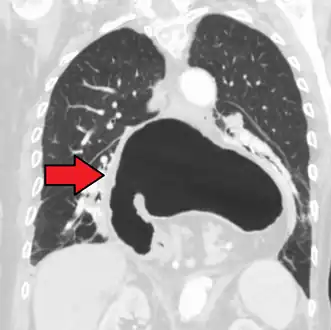

Diagnosis

The diagnosis of a hiatal hernia is typically made through an upper GI series, endoscopy, high resolution manometry, esophageal pH monitoring, and computed tomography (CT). Barium swallow as in upper GI series allows the size, location, stricture, stenosis of oesophagus to be seen. Besides, it can also evaluate the oesophageal movements. Endoscopy can analyse the esophageal internal surface for erosions, ulcers, and tumours. Meanwhile, manometry can determine the integrity of esophageal movements, and the presence of esophageal achalasia. pH testings allows the quantitative analysis of acid reflux episodes. CT scan is useful in diagnosing complications of hiatal hernia such as gastric volvulus, perforation, pneumoperitoneum, and pneumomediastinum.[8]